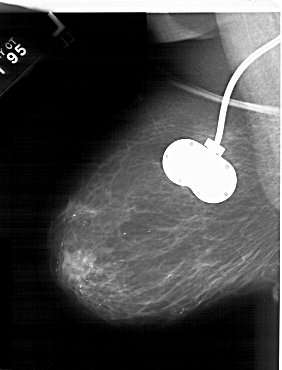

A_1532_1.RIGHT_MLO

RIGHT_MLO LINES 5776 PIXELS_PER_LINE 4921 BITS_PER_PIXEL 12 RESOLUTION 43.5 OVERLAY

FILE: A_1532_1.RIGHT_MLO.OVERLAY

TOTAL_ABNORMALITIES 1

ABNORMALITY 1

LESION_TYPE MASS SHAPE OVAL MARGINS ILL_DEFINED

ASSESSMENT 4

SUBTLETY 3

PATHOLOGY MALIGNANT

TOTAL_OUTLINES 1

BOUNDARY